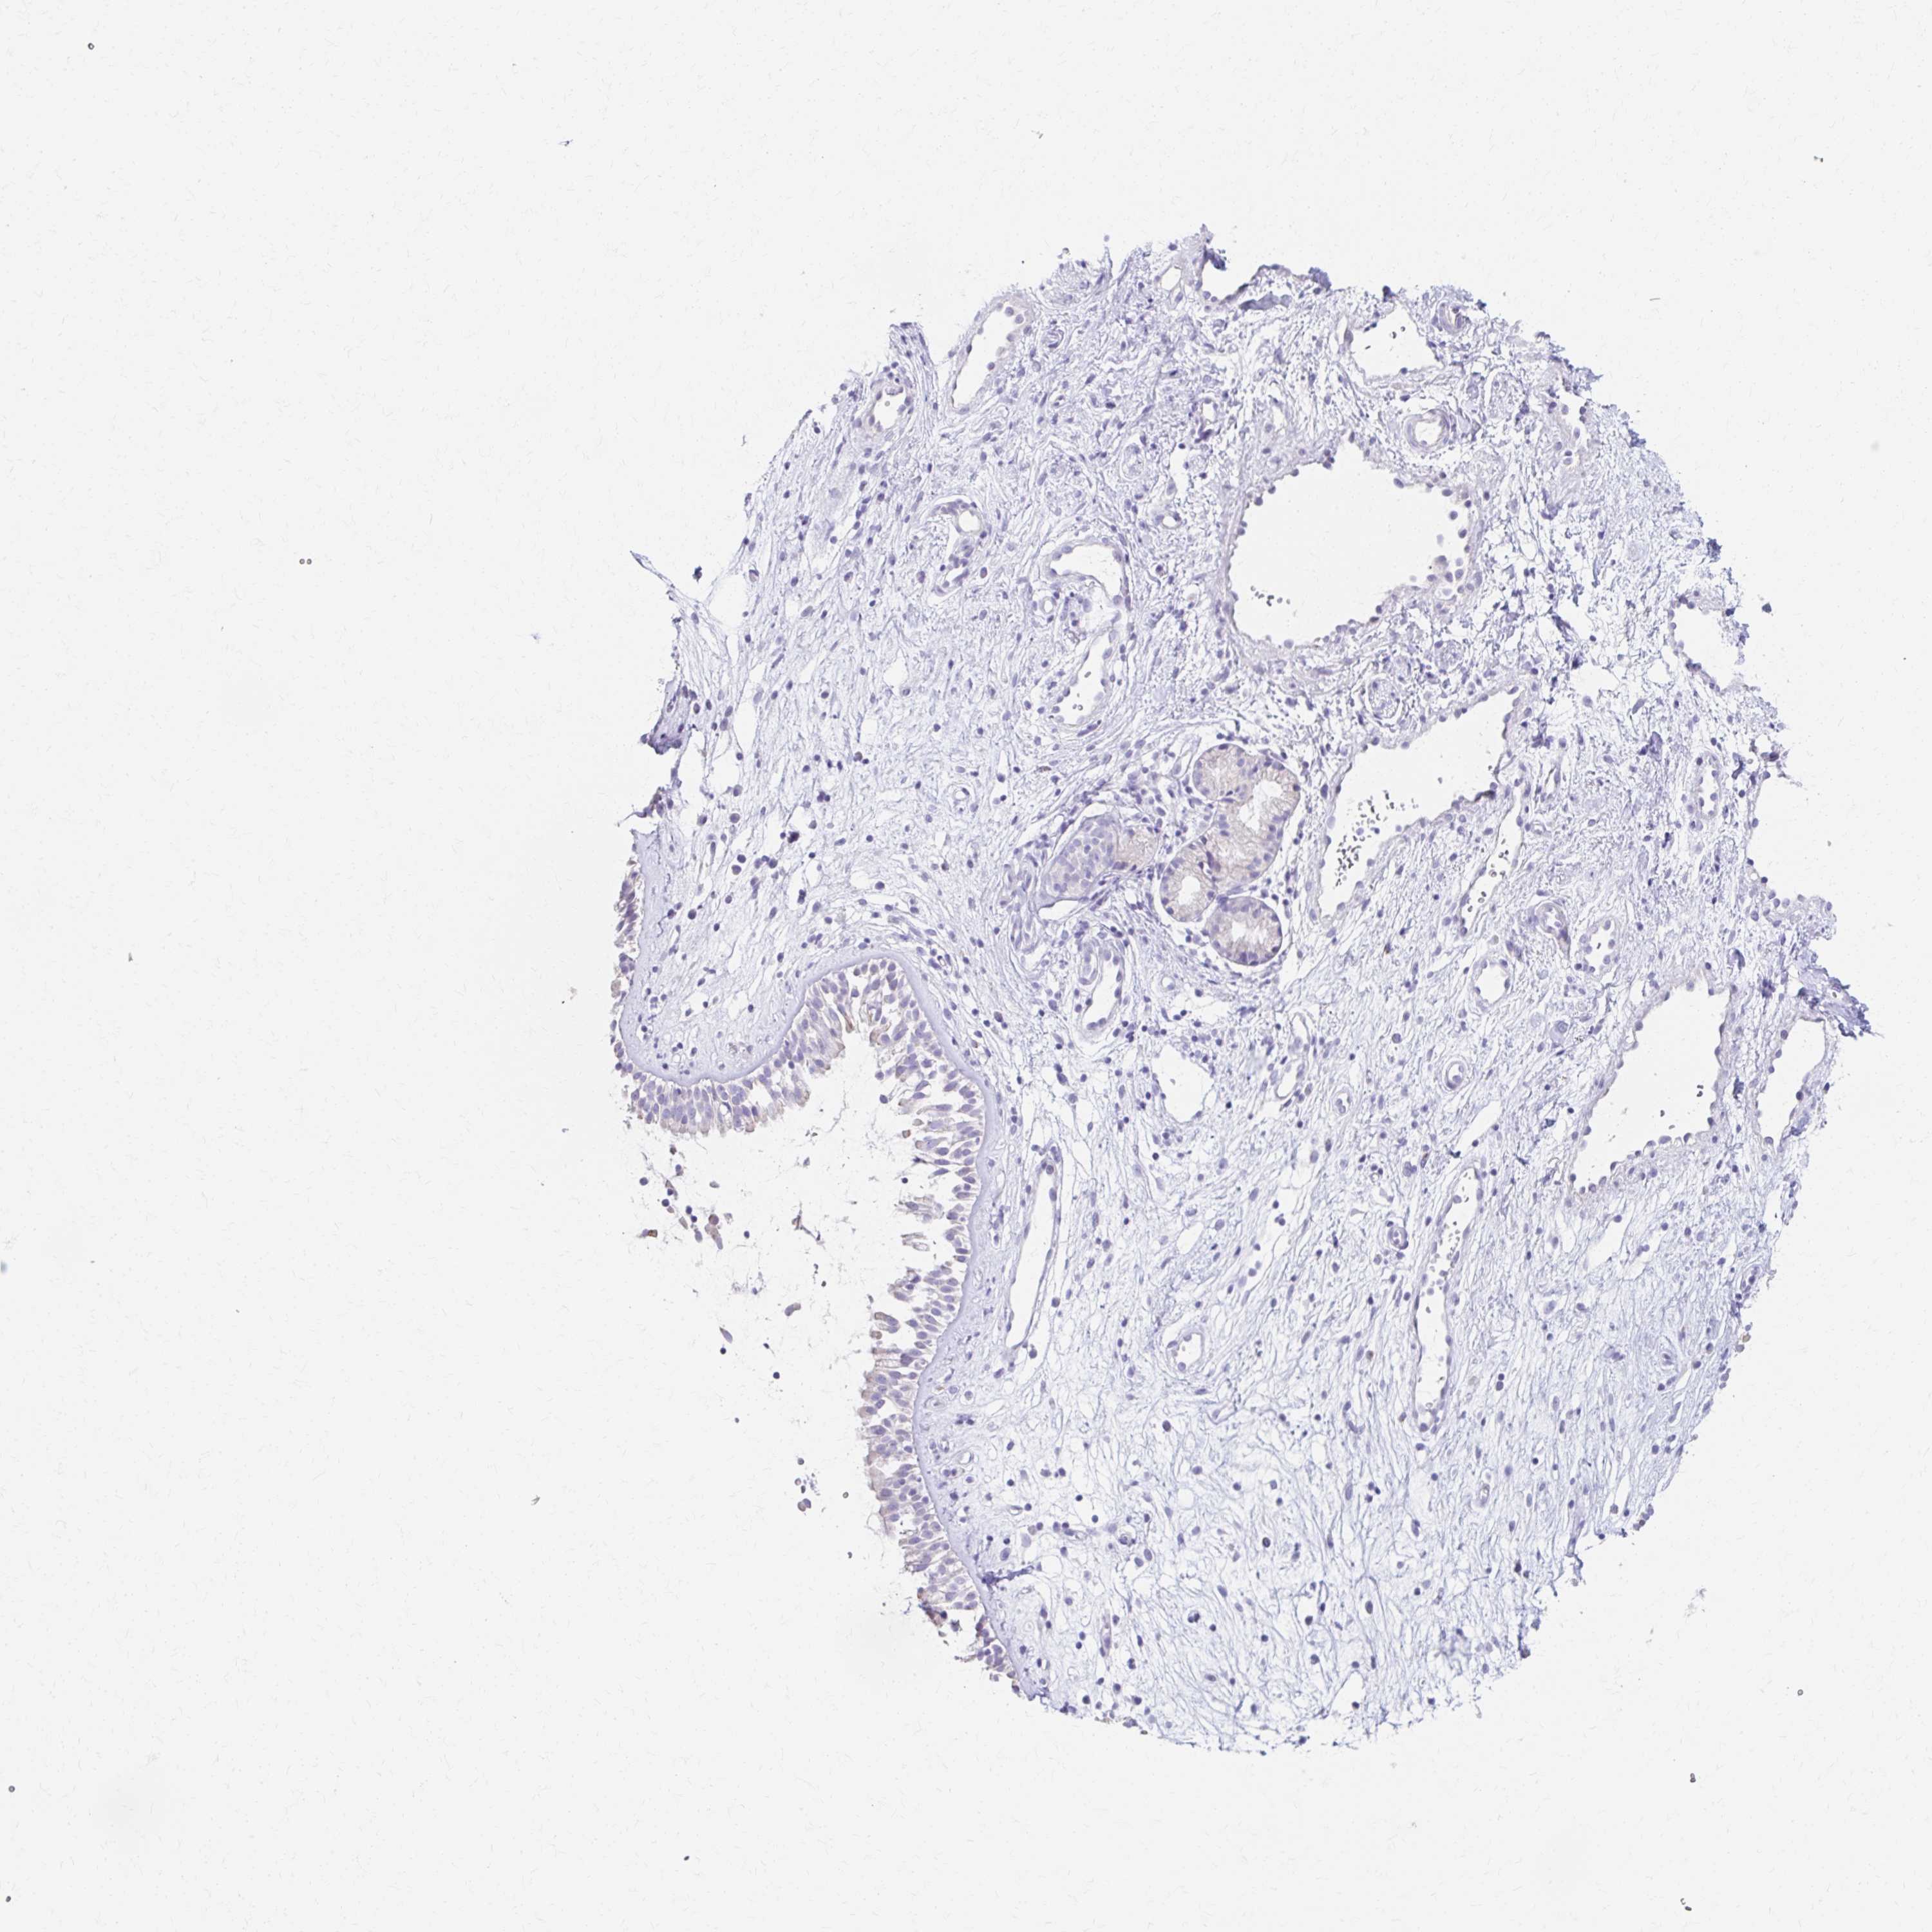

PRKCG